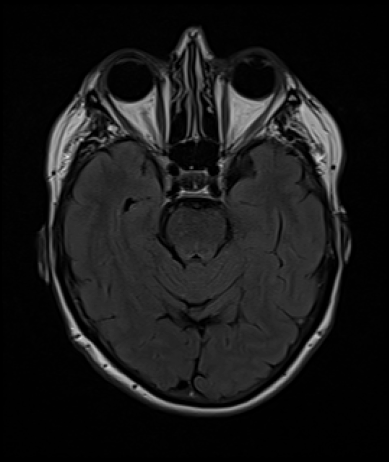

IRM T1

FLAIR

Test de robustesse du logiciel d'IA générative BrainGML-AD® (Société Geodaisics)

Objectif : Corréler les données de la ponction lombaire à celle de la morphométrie cérébrale issues de données IRM de patients atteints de la maladie d'Alzheimer par rapport au sujets avec plaintes subjectives et patients atteints d'autres maladies neurodégénératives.

Apports de Colybri :

✅ Mise à disposition d'une base de données structurée

✅ Sélection d'IRM Cérébrales

✅ Sélection de ponctions lombaires